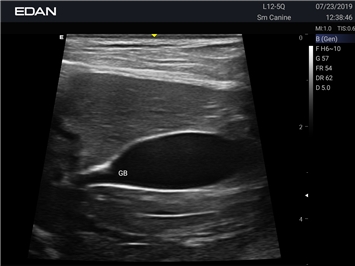

Ветеринарный ультразвук одним нажатием. Система Acclarix AX2 VET разработана с целью обеспечить бескомпромиссную производительность по доступной цене. Наличие уникальных двойных аккумуляторов в легком корпусе массой 4,5 кг из магниевого сплава позволяет системе Acclarix AX2 VET удовлетворять все потребности ветеринарных исследований, сохранив низкую стоимость.

EDAN Acclarix AX2 VET представляет собой специализированную ветеринарную ультразвуковую систему, сочетающую высокую производительность с доступной ценой. Благодаря продуманной конструкции и передовым технологиям, система обеспечивает качественную диагностику животных различных видов.

B-режим, Двухмерное сканирование:

Да